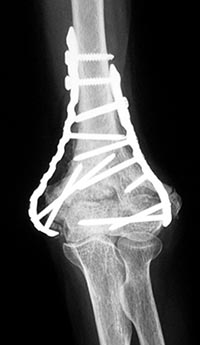

- 手術的治療:全身麻酔で、骨折を整復した後に金属のプレートやスクリューを用いて骨折した部分を固定します(図5,7)。特に希望がなければ、プレートやスクリューは抜去しません。

図5.上腕骨通顆骨折:金属プレートを2枚使用し、スクリューで固定しました。